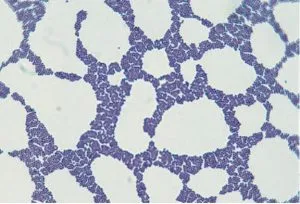

Calcofluor White Staining

It is commonly used to directly detect fungal elements and to observe the subtle characteristics of fungi grown in culture. The cell walls of fungi will bind the stain calcofluor white, which greatly enhances the visibility of fungal elements in tissue or other specimens.